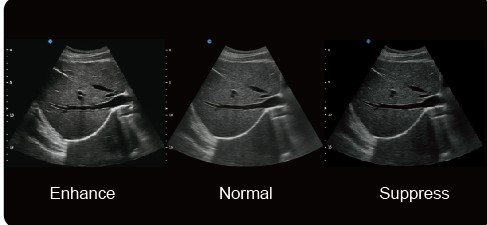

х-contrast - технология позволяет настраивать в одно касание контрастность и разрешение изображения, основываясь на разной плотности тканей. Три режима: повышенный (enhance), нормальный (normal) и пониженный (suppress).